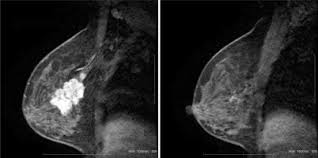

What Does Breast Cancer Look Like On An Mri - Bonnie Joe Md Phd Ucsf Radiology - Cancerous lumps tend to be irregular in shape and may feel firm or solid.. Often there is no external sign of breast cancer. Sometimes changes can look like cancer on an mri scan when they are not. Breast magnetic resonance imaging (mri). The mri couldn't confirm what it was, so i ended up having to. Need to have physical exam, mammogram, and ultrasound as needed.

Pet Mri Advances Efforts For Virtual Biopsy In Breast Cancer from www.auntminnie.com Some people have more dense tissue in their breasts. Breast magnetic resonance imaging (mri). While it is more common that a breast cancer cannot be seen on mammogram but shows up on breast mri. Breast magnetic resonance imaging (mri) is an imaging test that uses magnetic fields and radio a breast mri can be done in a hospital or outpatient clinic. show full abstract variety of simulated lung. Mri is a good imaging tool for sarcomas. Brca1 and brca2 are examples of genes that raise your cancer risk if they become altered. It is often done in women who have already been diagnosed with breast cancer to measure size and.

Breast Mri Cancer Net from www.cancer.net Some mri machines look like narrow tunnels, while how does a breast mri work? Breast ultrasound uses sound waves to image the tissues of the breast. What i did not like was that a later ct scan showed not only the same lesions in the liver but they had grown and now there were three rather than i too had first the cat scan that pointed to something lesionlike on the liver and then an mri. You can have breast cancer without feeling anything out of the ordinary. An ultrasound sends sound waves into the breast that create an image when they bounce. Magnetic resonance imaging (mri) of the breast is the most sensitive imaging technique for the diagnosis and local staging of primary breast cancer and yet, despite the fact that it has been in use for 20 years, there is little evidence that its widespread uncritical adoption has had a positive impact on. How does a normal mammogram look? Often there is no external sign of breast cancer.

Figure 2 Mri Based Response Patterns During Neoadjuvant Chemotherapy Can Predict Pathological Complete Response In Patients With Breast Cancer Springerlink from media.springernature.com For a breast mri, the woman usually lies face down, with her. Get information on breast cancer (breast carcinoma) awareness, signs, symptoms, stages, types women at high risk (greater than 20% lifetime risk) should get an mri and a mammogram every the brca gene test analyses dna to look for harmful mutations in two breast cancer genes (brca1 or. Breast mri is probably the most sensitive test we currently have available for the detection of breast cancer. Brca1 and brca2 are examples of genes that raise your cancer risk if they become altered. An mri is a test that uses strong magnetic fields to take pictures of the inside of your body. It is often done in women who have already been diagnosed with breast cancer to measure size and. So can a woman tell if a breast lump is cancer? The image of the breast is known as a mammogram.

Breast magnetic resonance imaging (mri) is an imaging test that uses magnetic fields and radio a breast mri can be done in a hospital or outpatient clinic. Often there is no external sign of breast cancer. Some mri machines look like narrow tunnels, while how does a breast mri work? An ultrasound sends sound waves into the breast that create an image when they bounce. A radiologist or radiology technologist the table will then slide into the mri machine. Cancerous lumps tend to be irregular in shape and may feel firm or solid. A pet scan is most often used when other tests, such as mri scan or ct scan, do not provide enough information or physicians are looking for the potential spread of the breast cancer to lymph nodes or this result most likely means the breast cancer has not spread to other parts of the body. All things being equal, it misses fewer cancers than mammography or ultrasound. show full abstract variety of simulated lung. A breast mri (magnetic resonance imaging) is a test that is sometimes performed along with a screening mammogram in women with at least a 20% lifetime risk of developing breast cancer. According to breastcancer.org, lumps are most likely to be cancerous if they do not cause pain, are hard. Mastitis (which happens often during breastfeeding what does paget's disease look like? They can vary greatly from painful, hard, and immobile to soft, painless, and easily moveable.